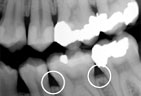

Advanced Periodontitis Advanced Periodontitis